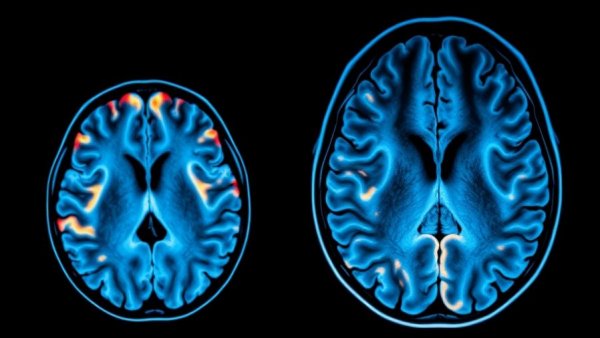

MRI scan illustrating menopause grey matter loss, colorful brain visualization.

Menopause can significantly impact women's mental and cognitive health as new research reveals a concerning connection between menopause and grey matter loss in key brain regions. Conducted by scientists at the University of Cambridge, the study has revealed that as women transition through menopause, they may experience reductions in grey matter volume linked to critical cognitive functions such as memory and emotional regulation.

Future Links to Dementia Risks